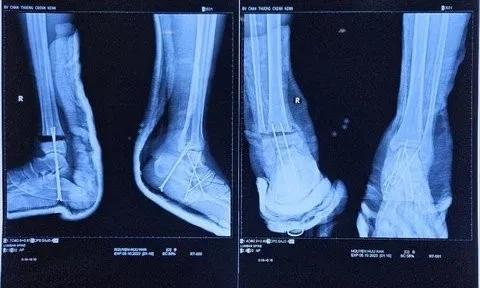

Hy hữu bệnh nhân bị đứt lìa cổ chân được phẫu thuật kịp thời

Ngày 14/10, bệnh nhân ở Bến Tre bị máy cắt cỏ cắt đứt lìa cổ chân, được bác sĩ phẫu thuật kịp thời.